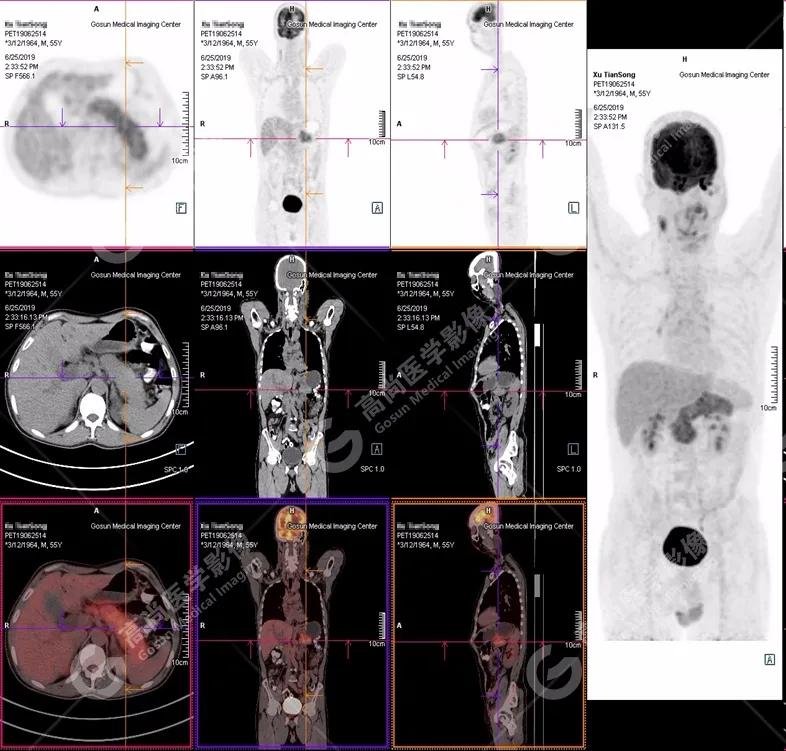

PET/CT全身图

胰腺肿胀、密度均匀,代谢弥漫性不均匀增高,SUV最大值5.2 平均值4.0

(1)胰腺轻度肿胀,胰腺体尾部胰管狭窄,未见明显占位性病变,代谢弥漫性增高。

(2)胰周(胰胃间隙)稍大淋巴结,代谢增高。

(3)全身其它部位未见明显高代谢恶性肿瘤征象。

PET/CT诊断

自身免疫性胰腺炎,伴胰周淋巴结炎性增生。